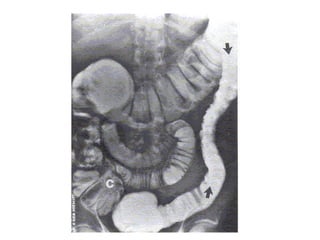

Signo del "remolino"(flecha).

OI secundaria a cáncer de colon ascendente (flecha blanca)

con dilatación de ciego (flecha negra)

e intestino delgado por incompetencia de válvula ileocecal.

OI secundaria a hernia externa

Cálculo impactado en íleon (flecha).

OI secundaria a enfermedad de Crohn

que compromete el íleon distal (flecha).